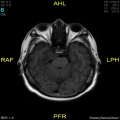

Male, Age 45

患者于1月前体检CT检查提示:右侧鞍旁及桥脑旁占位性病变,脑膜瘤可能。后于江苏省人民医院复查头颅MRI提示:右侧鞍旁占位,考虑脑膜瘤可能,病灶累及及小脑幕。病程中,患者右眼间断性活动受限,可缓解,无头痛头晕等其他不适。

右侧岩斜区肿瘤组织

灰红碎组织一堆,合计大小3.5*3*1.3cm。

T1

T2

T1增强